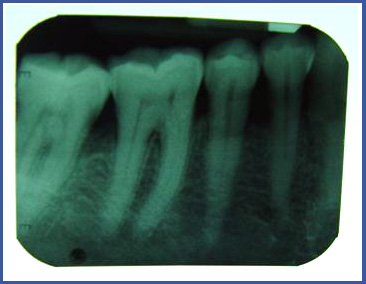

צילום פריאפיקאלי (PERIAPICAL)

זהו צילום בודד שנעשה במרפאת שיניים ומאפשר לראות את כל השן –כותרת והשורש וגם את הרקמה הקשה (עצם) סביב השורש.

צילום מסוג זה עושים בדר"כ בזמן טיפולי שורש , כאשר רוצים לבדוק האם ישנה דלקת סביב השורש או כאשר רוצים לבדוק את רמת העצם סביב השן.